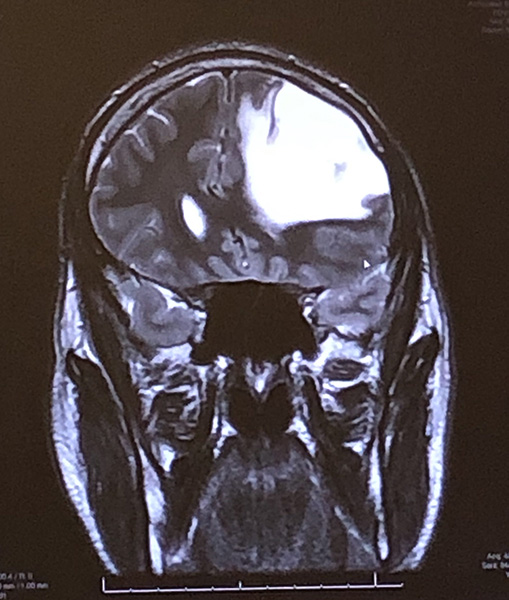

The journey began at the height of the COVID-19 pandemic in April 2020. Then 32, Nick suffered a midnight seizure that sent him falling from his bed. A CT scan revealed a mass the size of four golf balls in his left frontal lobe — later diagnosed as grade 2 astrocytoma.

“Voranigo has been incredibly successful for me,” Nick said. “Every time I go for an MRI, my neuro-oncologist says my tumor regrowth is shrinking. I’m grateful to not have side effects and avoid surgery, chemo, or radiation.”